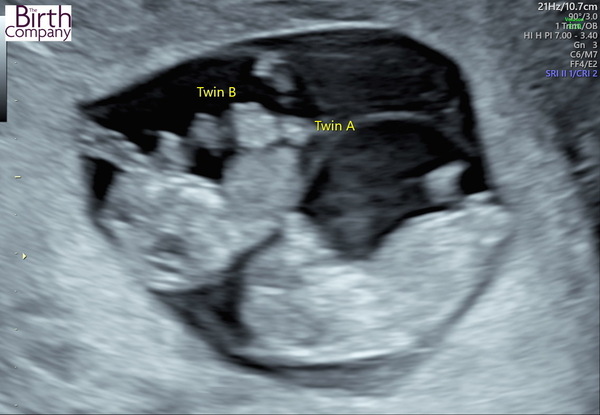

I had a private Harmony (NIPT) scan today, I saw & heard 2 strong heartbeats & we get the results for downs etc in a weeks time & we find the gender out at the same time. I will try to upload a pic, its still overwhelming, but i must admit I loved seeing them wiggling around, hopefully it will be better with time. X

Pic…

IVF Graduates due Summer 2022

@GingerBrummie Oh wow look at them!!! Gosh 2 little babies!! So glad you've had a scan and they both look healthy. That's so exciting that you find out the gender soon!!

I'm not entirely sure how it works, are they in the same sac together? 2 placentas?!